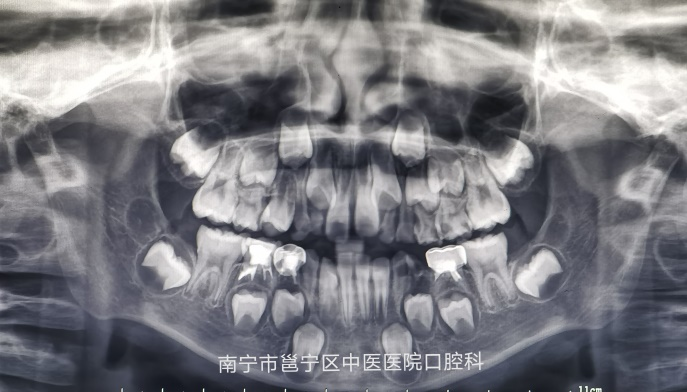

口腔曲面断层X线摄影是通过专门设计的口腔曲面全景摄影X线机,将上颌骨、下颌骨、颞颌关节、上颌窦、鼻腔及全口牙齿的影像同时显示在1张体层照片上的摄影技术。口腔曲面断层摄影在医疗诊断中应用越来越广泛,它能为牙体疾病,牙齿矫治以及牙槽骨,颞颌关节的骨折骨病等多种疾病提供重要的信息。

(龋齿及阻生埋伏的尖牙)

(预估恒牙萌出时间及检查有无先天缺牙或多生牙)

通过拍摄全景牙片,我们可以清楚地知道牙冠、牙根、牙槽骨及关节等情况,及时发现问题,处理问题,以免耽误治疗时机。

我院口腔科引进了先进的进口数字化全景及头颅正侧位二合一机,拍摄时间短,成像清晰,可帮助医生快速诊断,欢迎广大患者前来咨询及口腔检查。